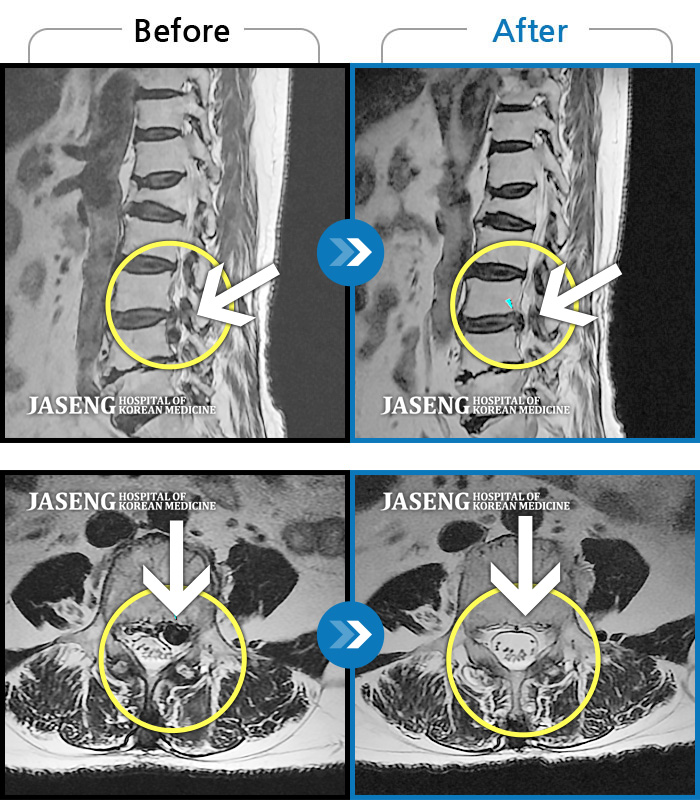

허리디스크

보라매 · 왕오호 원장

허리와 좌측 엉치 통증

촬영시기

2015.12.29 ~ 2018.10.11

2018.12.28

조회수 3,338